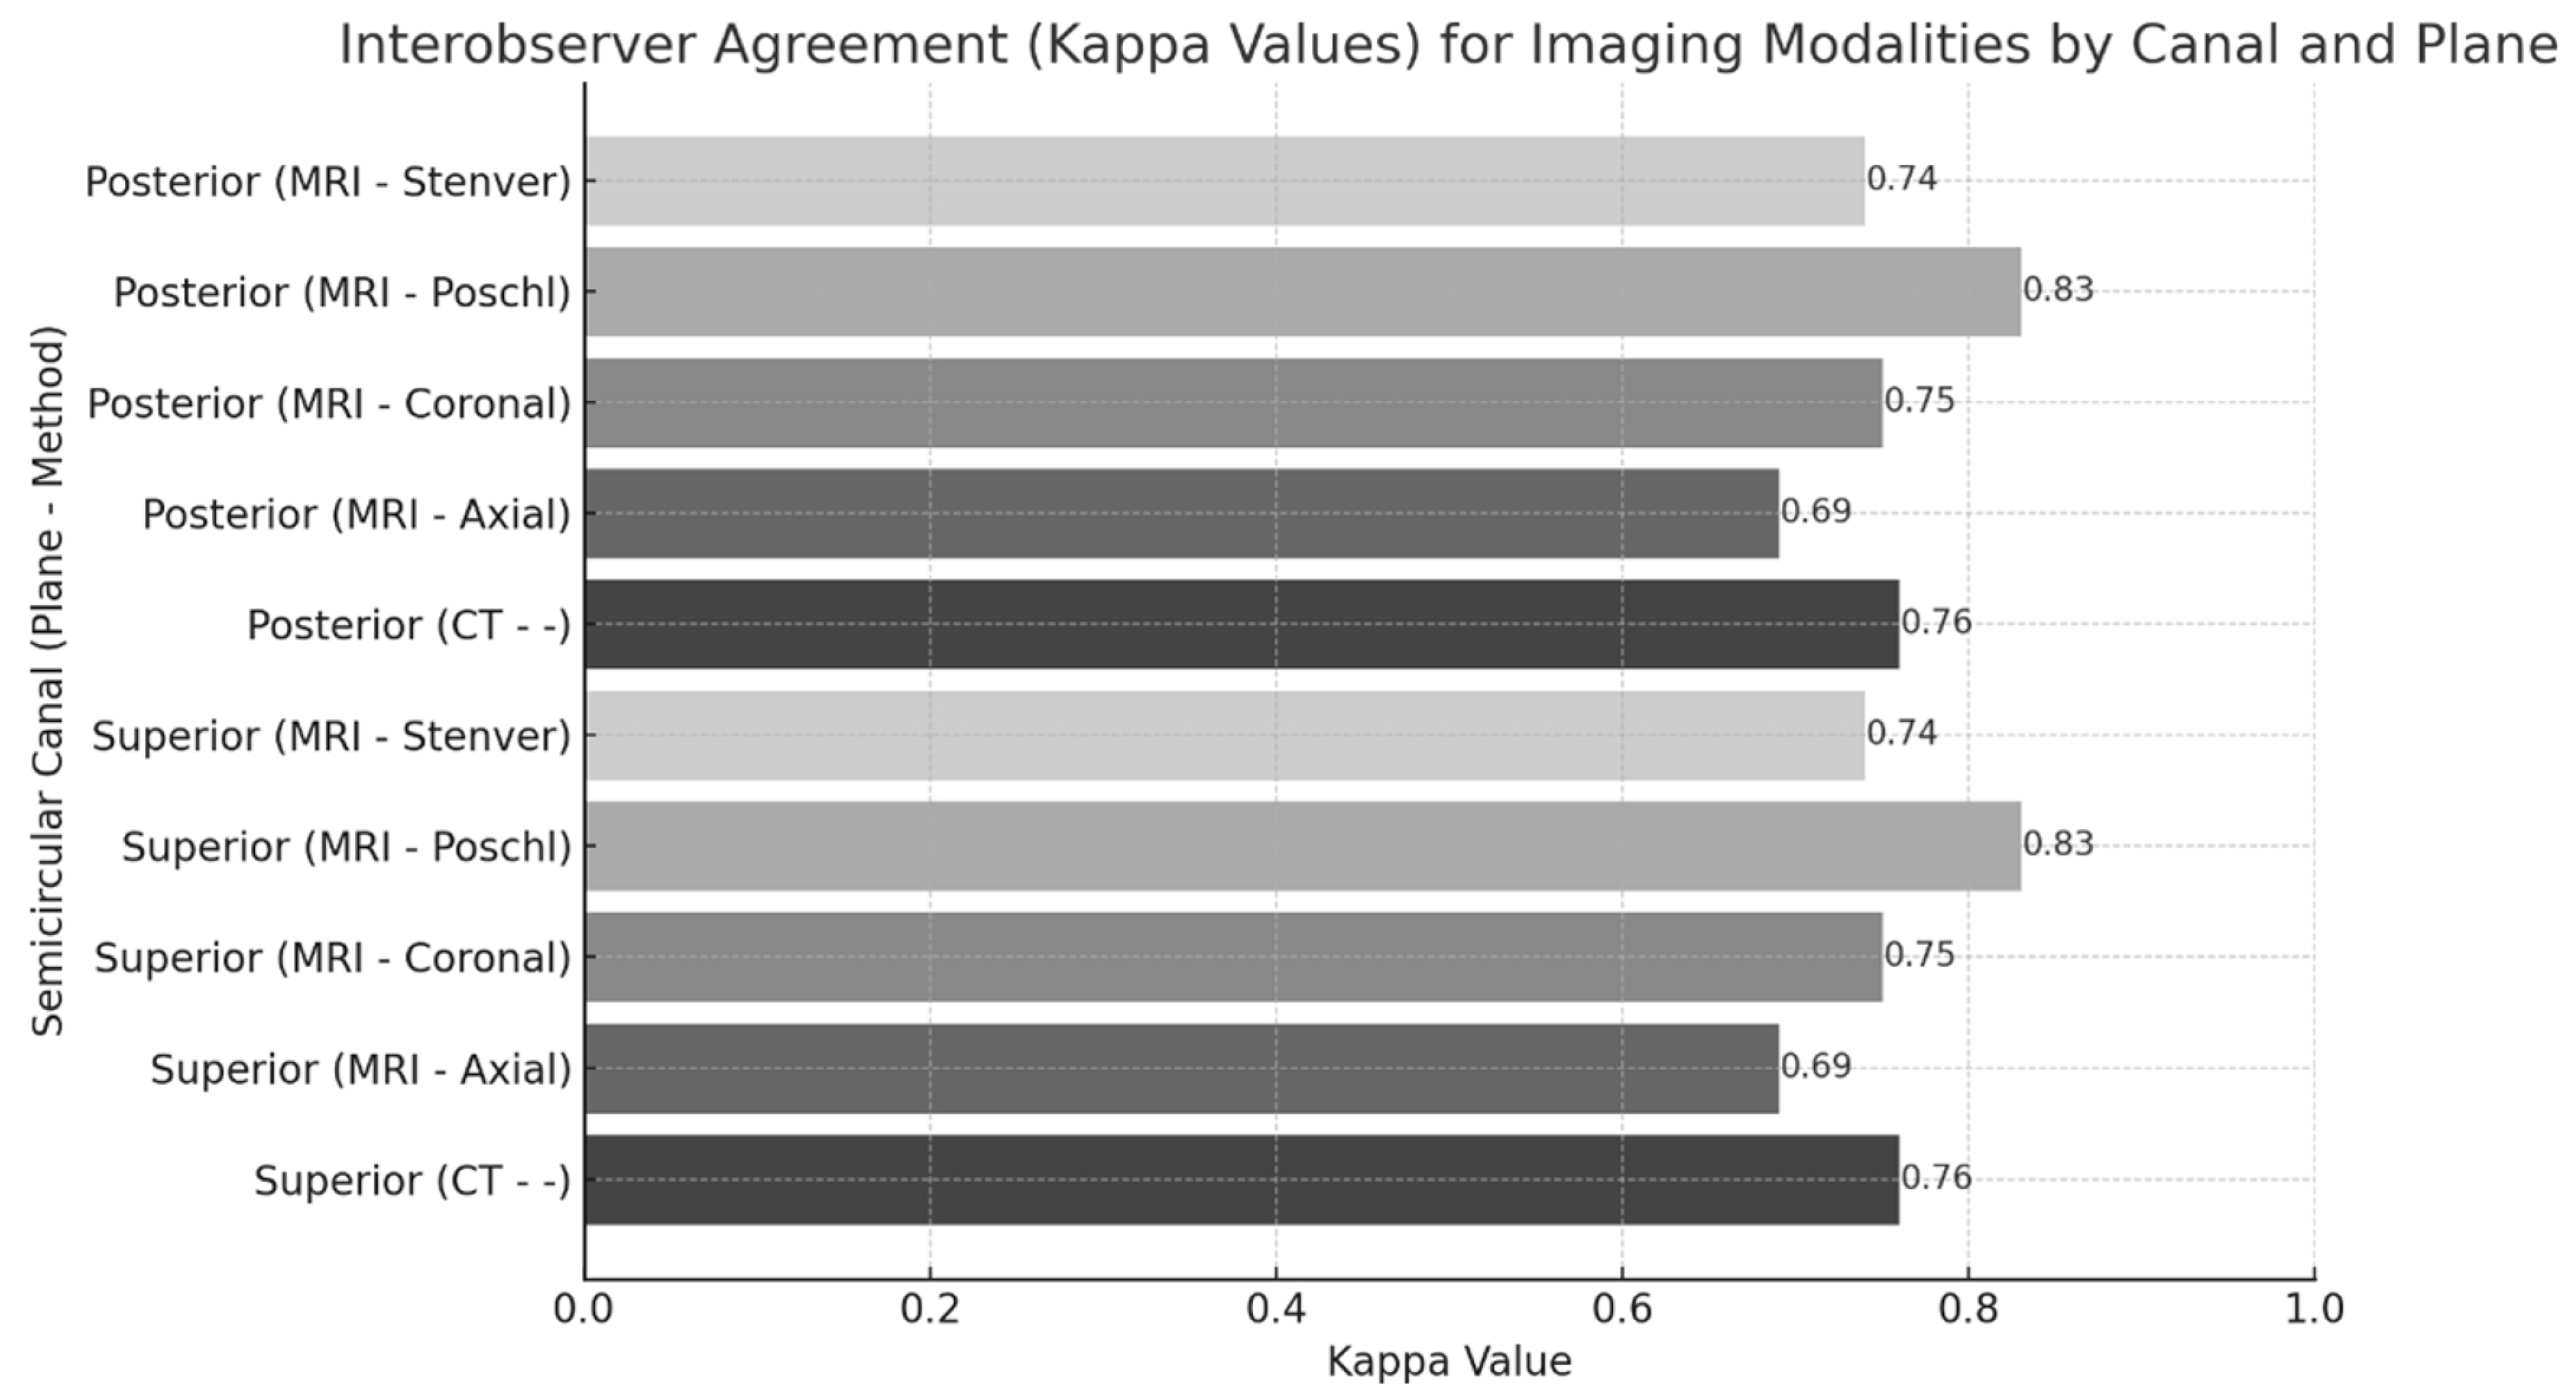

2.4. Statistical Analysis

3. Results

4. Discussion